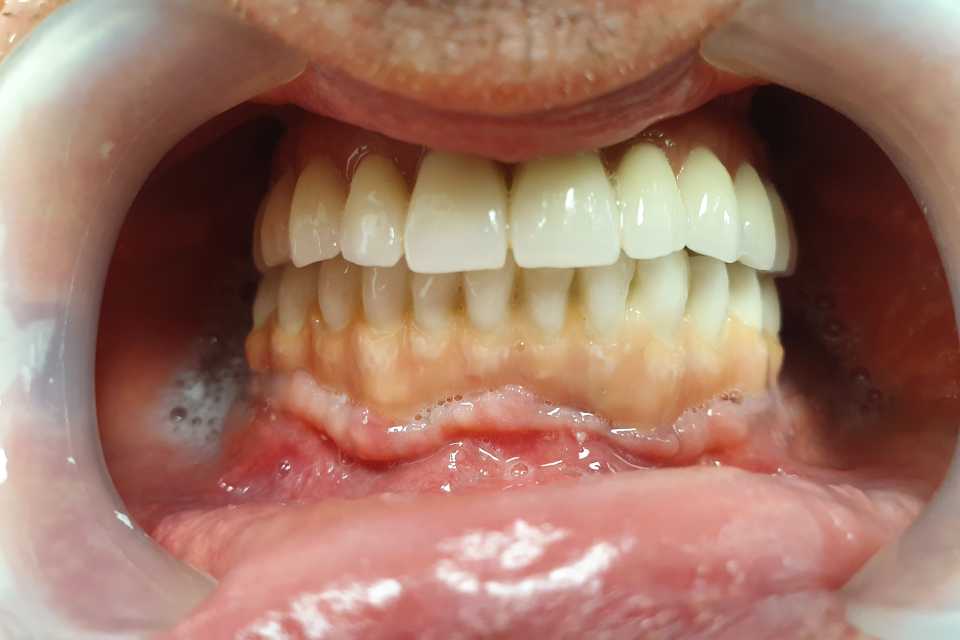

Pacientul a revenit in cabinet pentru consultatia anuala de intretinere, implanturile fiind inserate in urma cu 5 ani.

Cazul a fost unul foarte dificil pacientul fiind purtator vechi de proteze totale acrilice bimaxilar. A fost nevoie de 2 sinus lifting-uri si 5 implanturi pentru arcada superioara, iar pentru arcada inferioara s-au realizat aditii osoase (bilateral), prin tehnica Khoury.

Rezultatele au fost spectaculoase, fara sa fi intervenit resorbtii de natura osasa sau gingivala, pacientul fiind foarte multumit.